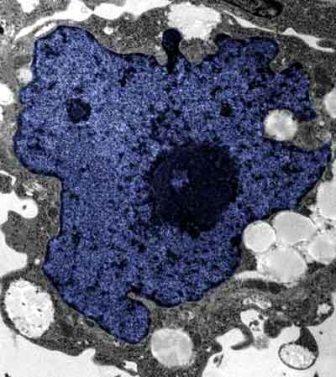

在成人體內及胚胎內發現的干細胞屬于主細胞,能發育成各種各樣的組織,可作為人體“修補工具箱”,取代死去及腐壞細胞組織。此前,最可行的干細胞為胚胎干細胞,但它的使用一直受到爭議,因為要在胚胎抽取干細胞會令胚胎死亡,有人認為這樣是變相奪走一條生命。

來自英國和加拿大的兩組研究員所用的新方法不必使用病毒。這項新突破暗示科學家現在能更認真地看待在醫學中利用皮膚干細胞(即誘導多功能干細胞,俗稱“iPs”細胞)的前景。

這些細胞只要配以適當的化學品和蛋白質,就能轉化成腦神經元、制造胰島素的胰腺細胞、骨或軟骨、心臟肌肉,或其它多種組織。這些細胞利用病人皮膚來培育,更暗示它們不會被人體排斥。